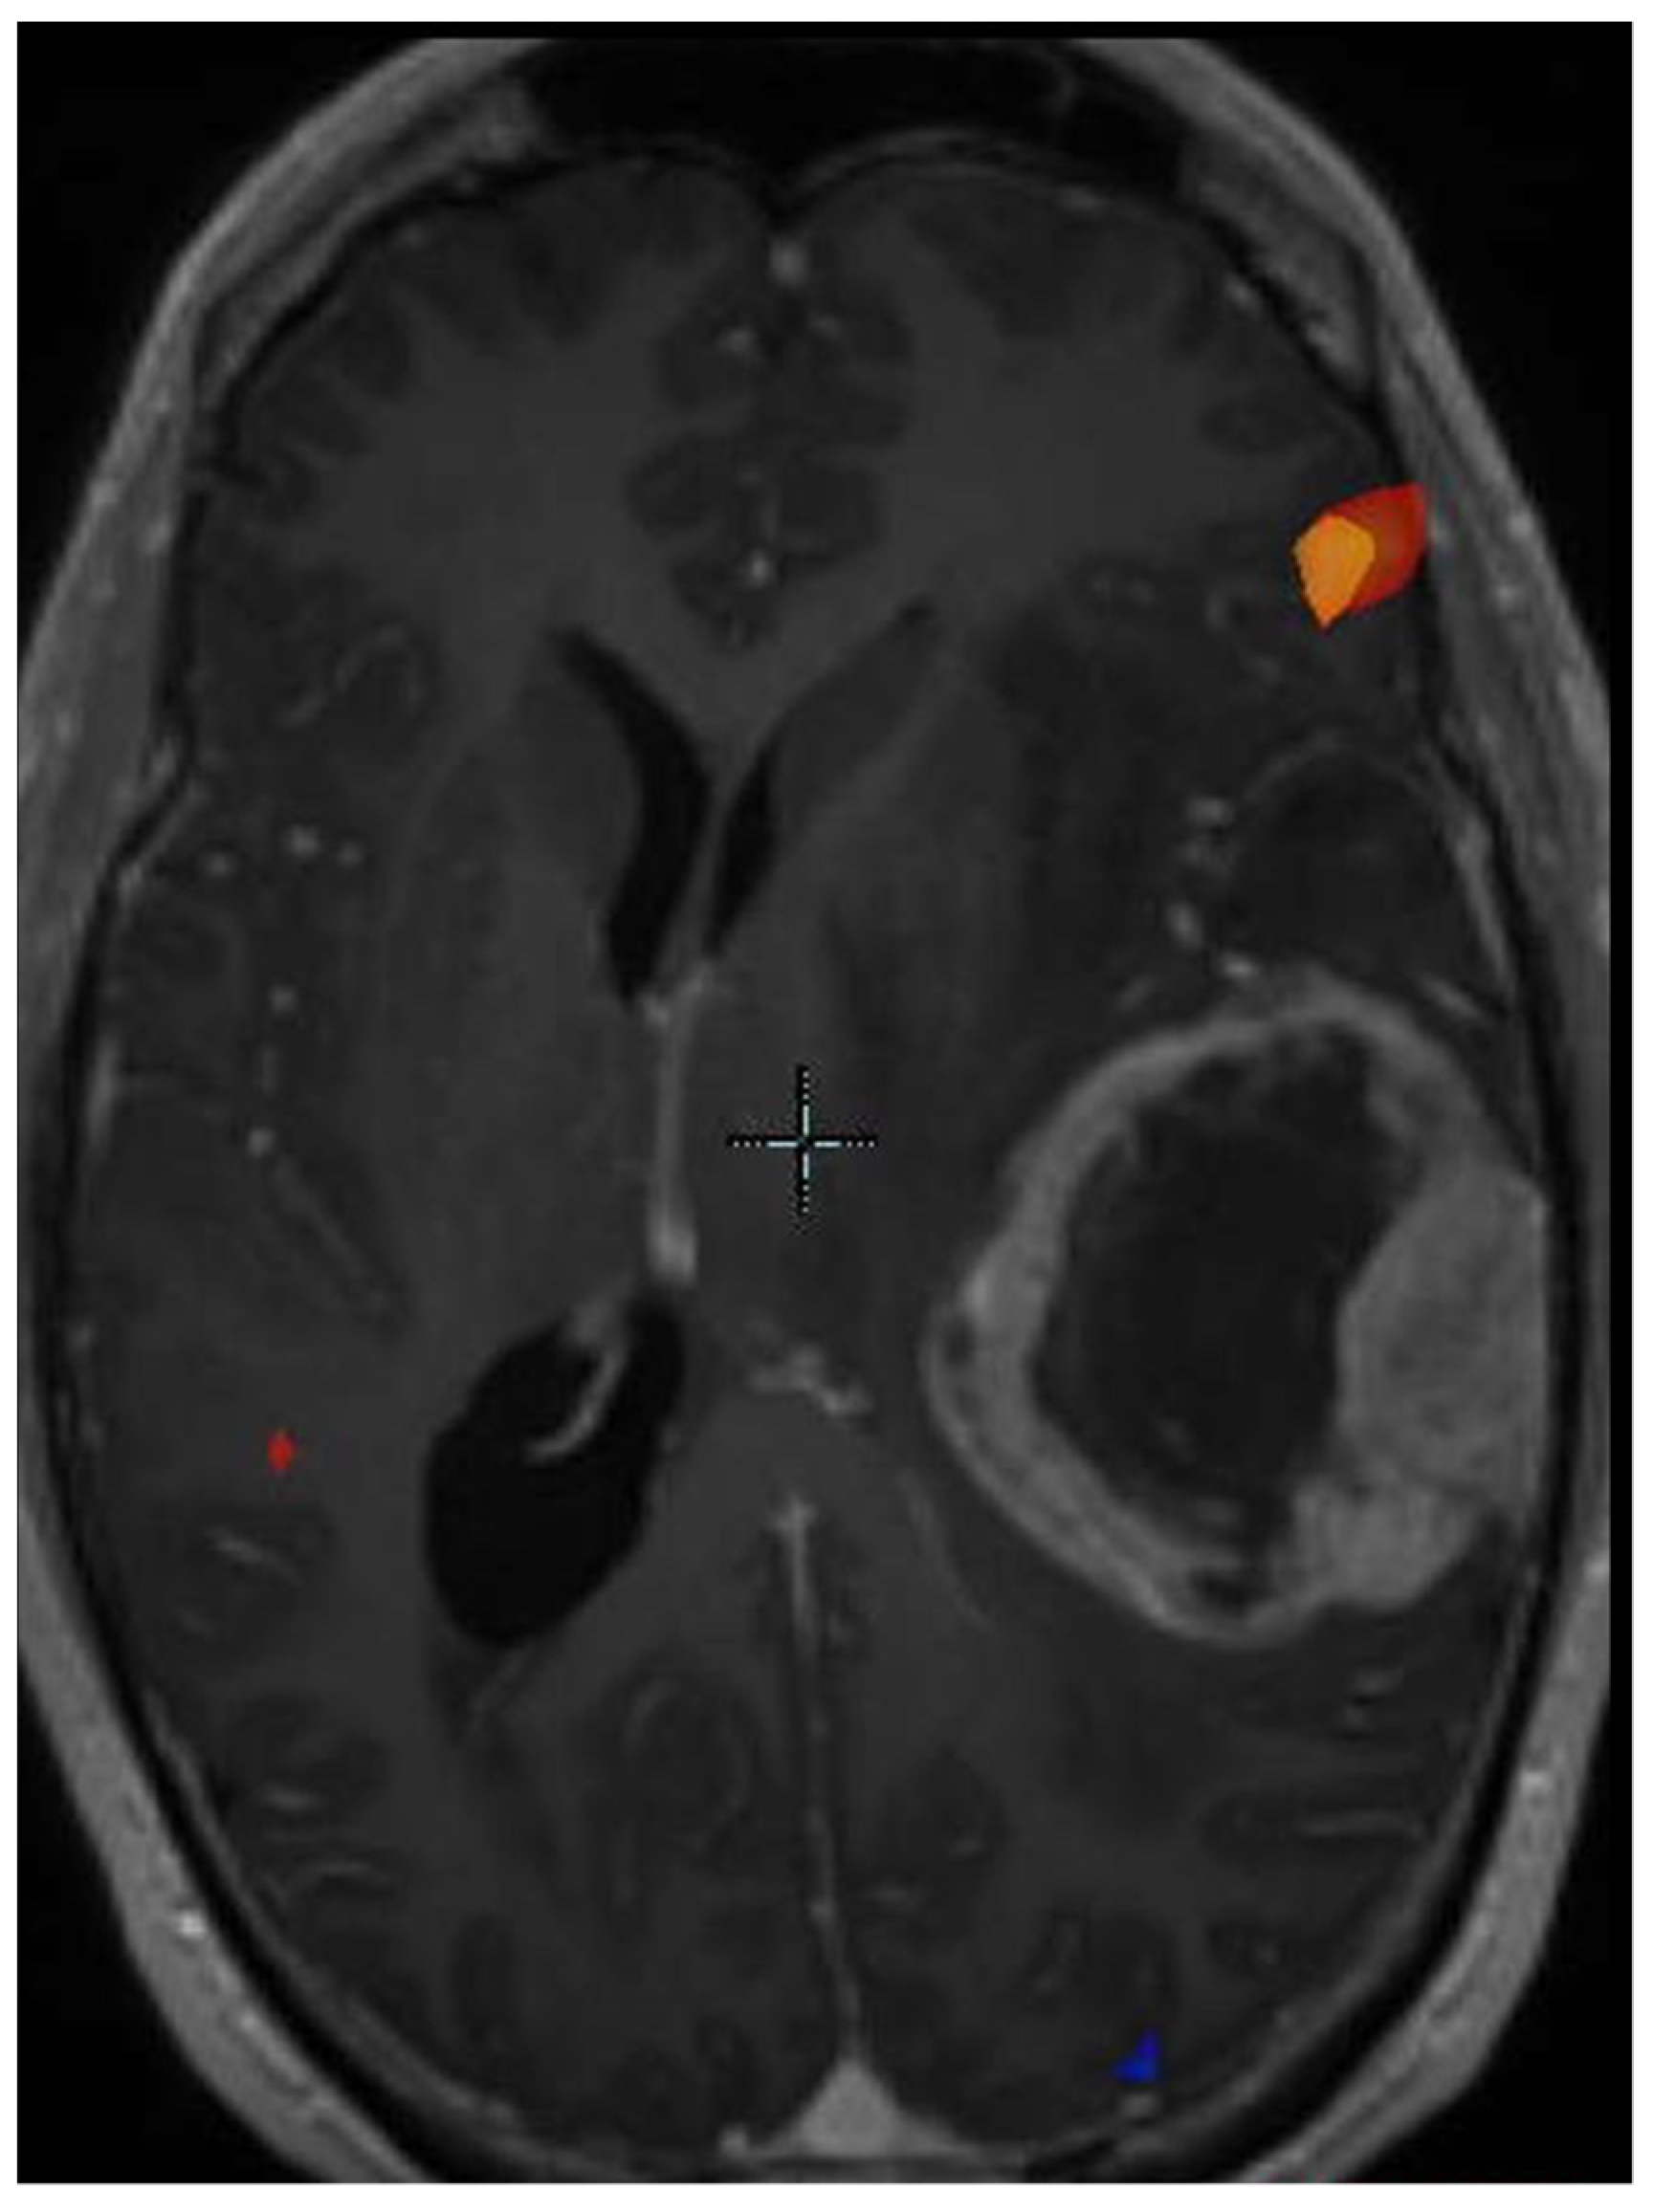

- Jones, K.K.; Maziero, D.; Ford, J.C.; Stoyanova, R.; Goryawala, M.; Diwanji, T.; Mellon, E.A. MRI-guided radiotherapy identifies early pseudoprogression of glioblastoma. Res. Sq. 2020. [Google Scholar] [CrossRef]